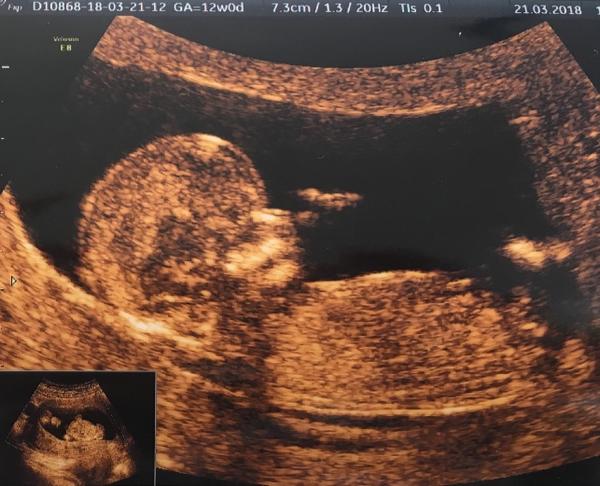

Ahoj 🙂 momentálně jsem ve 14tt. Ve 12+4tt jsem byla na screeningu v Ústí a zeptala jsem se, jestli jde už poznat nějaké pohlaví. Doktorka se na mě podívala a řekla mi, jestli si to přejeme vědět, ze je to za poplatek s 95% přesností. Tak jsem kývla a doktorka hned řekla, ze podle pohlavního hrbolku to vypadá na holcicku :D ukazala nám, jak by to vypadalo, kdyby to byl kluk a vše nám popsala. Ale já stejně stále přemýšlím a zkoumam fotku...Mimochodem každý kdo na tehle klinice byl, tak jim to pohlaví sdělili a opravdu to tak bylo. Tak co myslíte 🙂)

Tak pry to vypadá na holku...

@2hanah Je tam vidět jen pohlavní hrbolek 🙂. Pohlavi se určuje podle jeho sklonu. Když směřuje nahoru, tak kluk, když rovnoběžně se zakřivením páteře, tak holka. Na velký ultrazvuk jdu az za 2 týdny 🙂. Ovšem zatím většina tipovala holcicku... Sama jsem zvědavá, co to je... Na druhou stranu přemýšlím, jestli si nenechat překvapeni do porodu 🙂